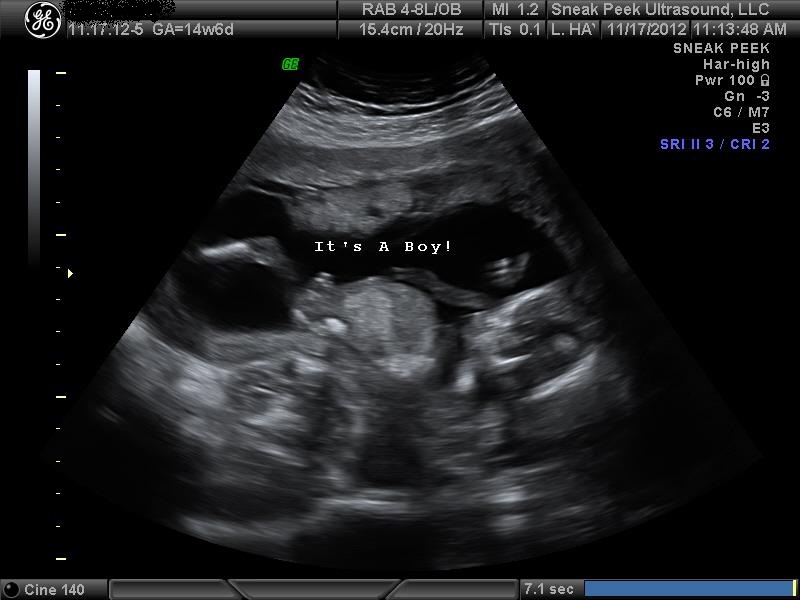

She said 100% boy... What do you think??Attachment 7090